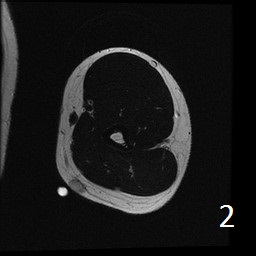

Angiolipoma is a subcutaneous benign tumor, made up of mature fat and blood vessels that often presents as multiple lesions. It sometimes arises intramuscularly. The incidence may be associated with familial heritage, close to 5% of the cases. Angiolipomas often arise in young patients, shortly before puberty, and are rarely seen in younger children or older adults. Angiolipomas often present as single or multiple subcutaneous tender to painful nodules (especially multiple ones). The pain may decrease as the lesion ages. No preference for ages or gender. Sites more commonly affected are the upper extremity and trunk, but rarely can affect head and neck region. MRI shows homogeneous and well circumscribed lesion, with intermediated signal on T1w (Fig. 1) and increased signal on T2W (Fig. 2). On fat suppress sequences the tumor may not suppress completely necause of its vascularity (Fig. 3). There is significant enhancement post contrast images (Fig. 4). On gross pathology the mass is a circumscribed, yellow-red nodular mass due high fat content and blood vessel proliferation. Microscopically, shows mature fat cells separated by branching network of small blood vessels, more prominent in subcapsular areas; there are usually associated fibrin thrombi (important sign). Adipocytes and interspersed vascular structures are seen, lined by elongated endothelial cells. These cells are irregular, and fingerlike extensions surrounded by periytes. Angiolipoma is a benign mass. It does not exhibit aggressive behavior. It rarely shows recurrence after resection. The treatment is complete surgical excision.

Fig. 1-4: Axial MRI of the arm shows a well circumscribed mass with intermediate signal on T1W (Fig. 1), and increased in T2W (Fig. 2). Fig. 3 Axial T1W FS shows a lesion and moderate intense on T1WFS post contrast (Fig. 4).